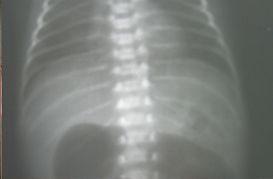

Atresia de Esofago

Atresia Intestinal

Enterocolitis

Gastrosquisis y Onfalocele

Hipertrofia de Piloro

Neo Natal y Lactante